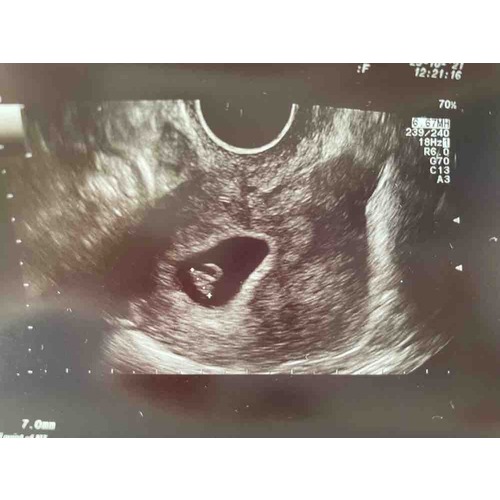

Source: freeirtbta.pages.dev Vruchtzakje+dooier geen vruchtje 6 weken en 4 dagen zwangerschapspraat 1 24baby Forum , Het vruchtzakje ziet eruit als een met vocht gevuld blaasje dat een wit/roze kleur heeft De temperatuur in het vruchtzakje is 37,6 graden celsius, dit is de ideale temperatuur voor de baby

Als je minder dan 6 weken zwanger bent, is het normaal dat er nog geen hartslag te zien is De temperatuur in het vruchtzakje is 37,6 graden celsius, dit is de ideale temperatuur voor de baby

Source: benkovicjcw.pages.dev Miskraam 6 weken + foto miskraam 1 24baby Forum , Wanneer je na 6 weken een miskraam krijgt, kun je een klein dooierzakje - vaak niet groter dan je pinknagel - zien De oorzaak van een miskraam bij 5 tot 6 weken zwangerschap ligt vaak in de aanleg van het vruchtje